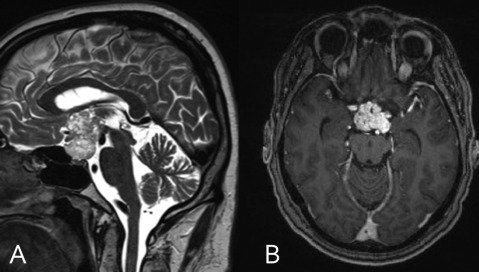

Dandy Walker malformation

agenesis/hypoplasia of cerebellar vermis resulting in cystic enlargement of 4th ventricle

can exist with or without hydrocephalus

can be hypotonic & ataxic